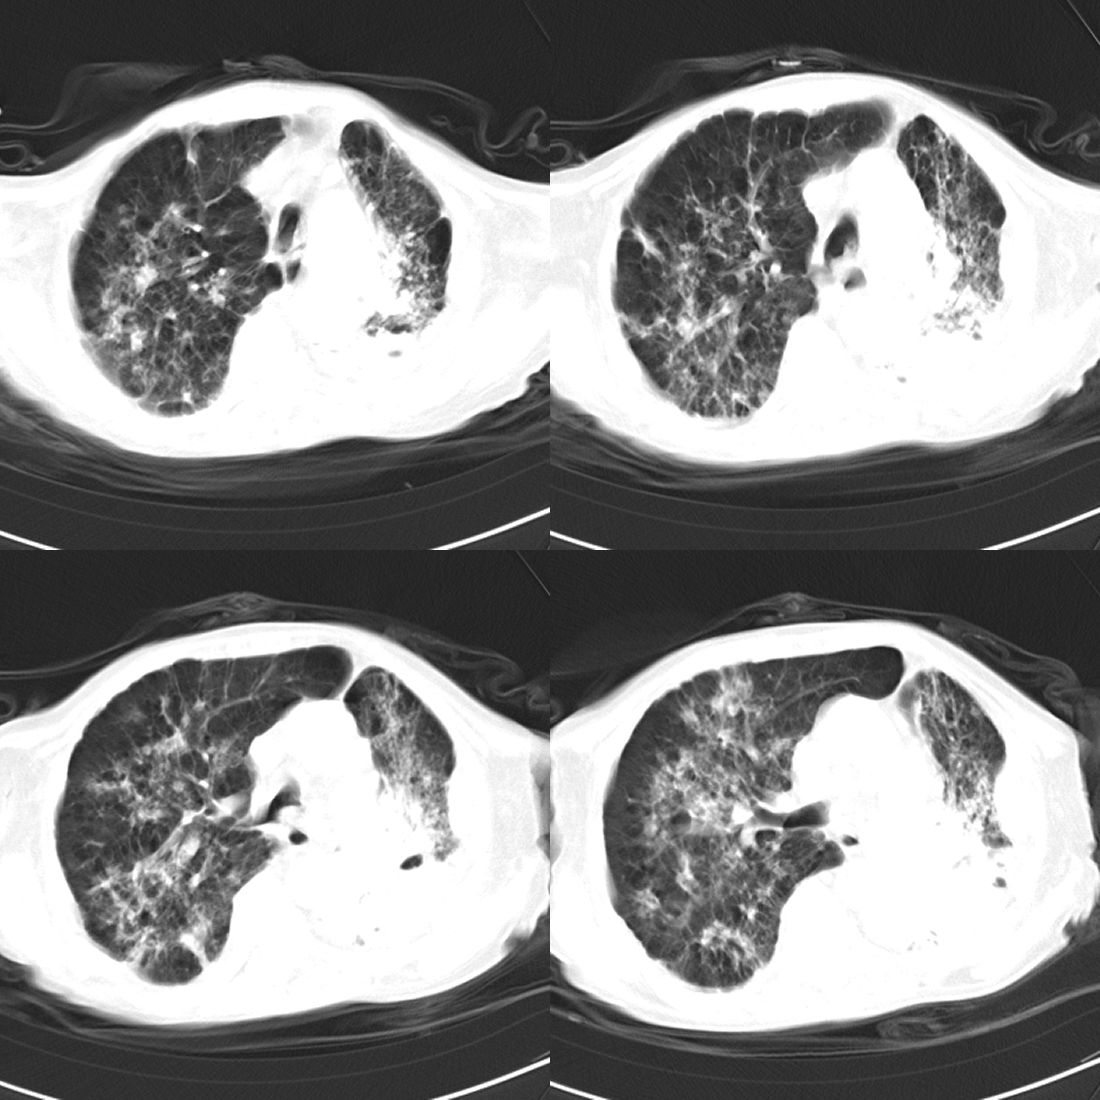

以下是引用zsl6918在2008-11-29 21:51:00的发言:[br]建议追问病史有无粉尘接触史,鉴别是结核还是矽肺。另外,左侧肺门的改变需强化明确,除外占位。

以下是引用liuyue在2008-11-30 6:01:00的发言:[br]双肺继发性肺结核;左侧包裹性积液;建议增强化或支气管镜检查除外左肺占位性病变.